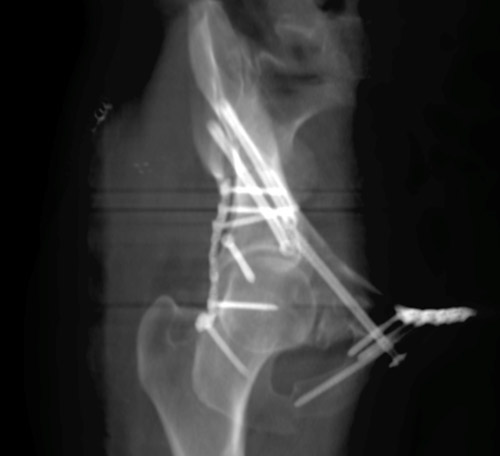

Pre-op X-Rays after applying correct amount of binder compression

Pre-op X-Rays

Final strategy decision

• The posterior pelvic injury was first anatomically reduced and stabilized by two iliosacral screws.

• Then the anterior column of the acetabulum was reduced and stabilised by 2 anteroposterior iliac screws and one retrograde anterior column screw, the symphysis was plated.

• Finally, the posterior column was reduced through a Kocher-Langenbeck approach and fixed to the anterior column with a magic screw and a posterior plate.